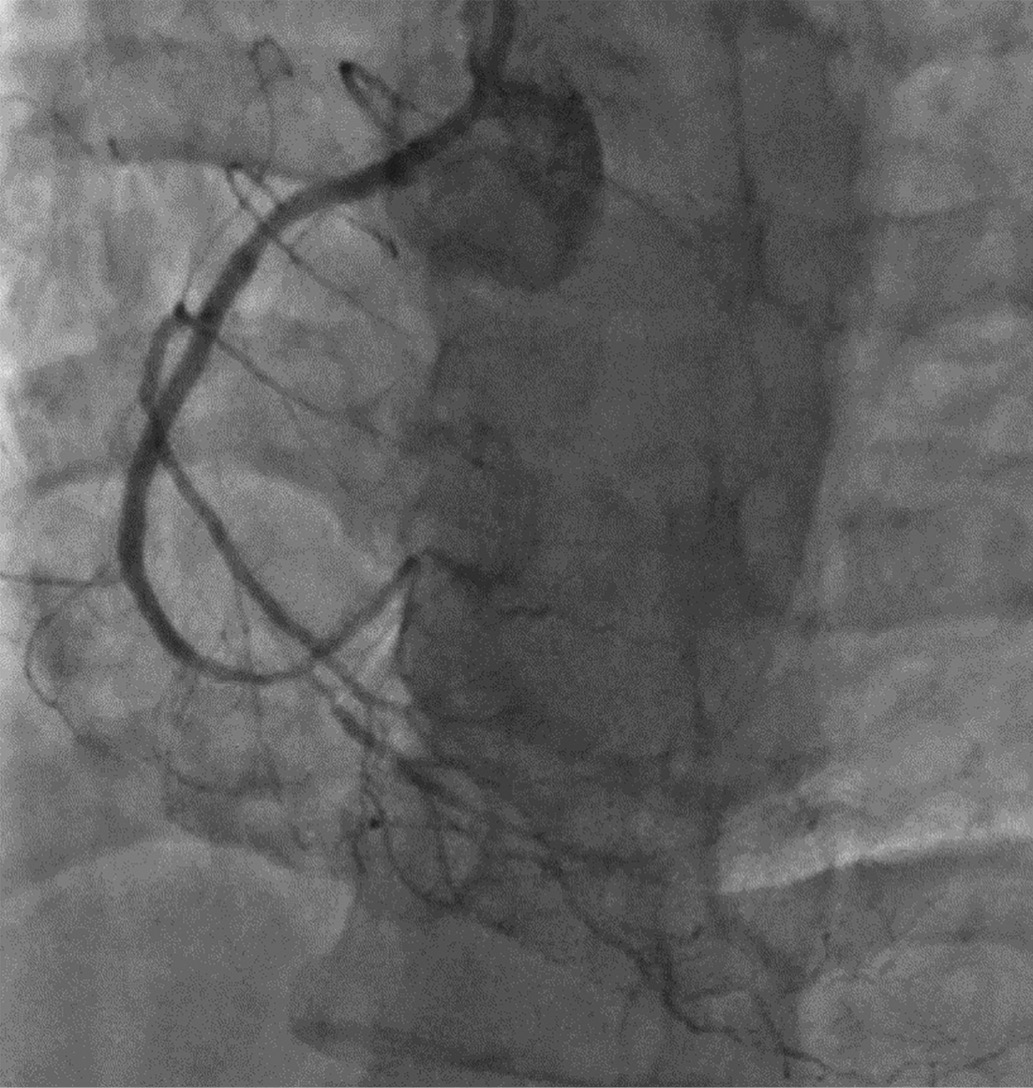

Вместе с тем причина выраженной систолической дисфункции ЛЖ оставалась неясна. Для уточнения ИБС как причины систолической дисфункции ЛЖ больному была проведена коронарография, на которой было выявлено: ствол левой коронарной артерии проходим; передняя межжелудочковая артерия (ПМЖА) — с диффузными изменениями на всем протяжении, малого калибра; стеноз в средней трети 70–90%; стенозы дистальной трети до 50%; диагональная артерия — малого калибра, тандемные субтотальные стенозы в проксимальной трети; огибающая артерия — неровные контуры проксимальной трети; 1-я ветвь тупого края (ВТК) окклюзирована в устье, малого калибра; постокклюзионные отделы контрастируются повнутрисистемным коллатералям; 2-я ВТК окклюзирована в проксимальной трети, малого калибра; постокклюзионные отделы контрастируются по внутрисистемным коллатералям; маргинальная ветвь — субтотальный стеноз в устье; правая коронарная артерия (ПКА) — неровные контуры проксимальной трети, окклюзия в средней трети; дистальные отделы контрастируются по внутри- и межсистемным коллатералям (рис. 1, 2).

Рисунок 2. Передняя межжелудочковая артерия.

Figure 2. Anterior interventricular artery.